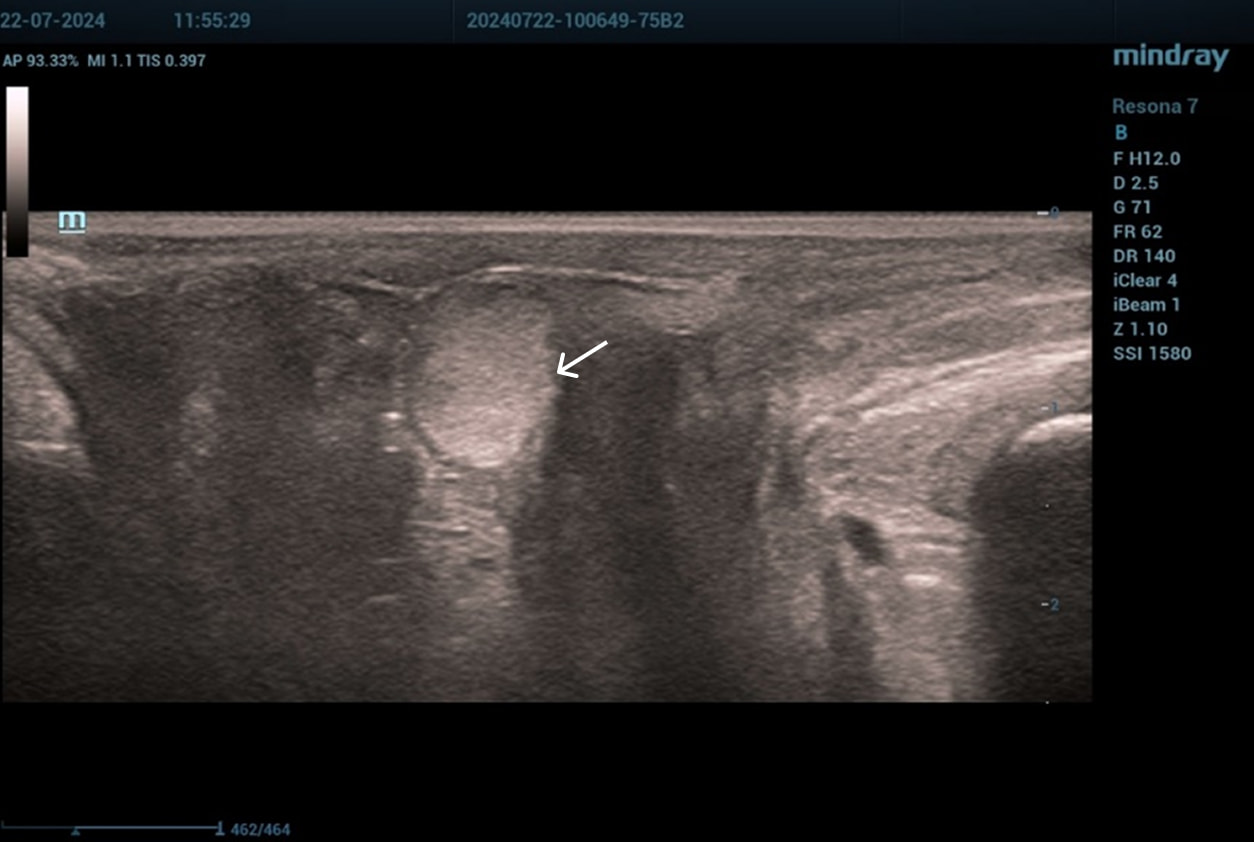

Эхограммы периуретральной области

Трансперинеальный доступ, линейный датчик.

Слева от уретры округлое образование с четкой капсулой и мелкодисперсной взвесью размерами 1,5×1,0 см (филлер с воспалением), справа — анэхогенное овоидное образование (филлер).

Эхограмма 1